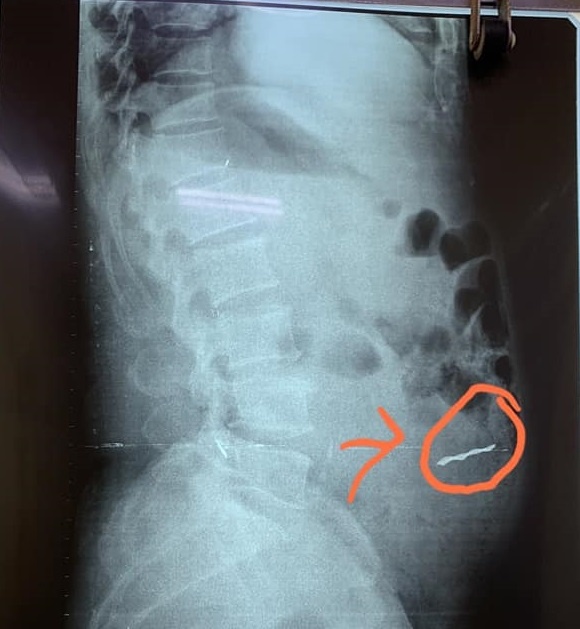

Sau khi thăm khám, chụp X-quang và làm xét nghiệm, các bác sĩ phát hiện dị vật cứng, dài khoảng 3 cm trong ổ bụng, gây thủng ruột non của bệnh nhân. Ông T. nhanh chóng được đưa lên phòng mổ cấp cứu, lấy dị vật ra khỏi ổ bụng và khâu lỗ thủng ruột.

Hình ảnh dị vật trên phim X-quang. Ảnh: BVCC.

Sau hơn một giờ phẫu thuật, các bác sĩ đã lấy ra miếng sắt dài 3,5 cm. Người đàn ông này được y bác sĩ khâu tổn thương, bảo tồn ruột và chuyển về khoa Ngoại điều trị.